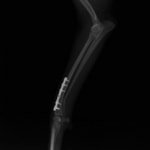

症例:交通事故による椎体脱臼

柴犬:9歳、避妊雌

交通事故直後、胸腰部に激しい疼痛、両後肢に完全麻痺を認め、シェフシェリントン徴候を呈していました。レントゲン検査において、第11-12胸椎間の脱臼が認められました。

脊髄の減圧、脊柱管の再構築・安定化を目的に、片側椎弓切除術およびMatrixMANDIBLE Plateによる椎体固定を実施しました。

隣接椎体を架橋するようにプレートを設置しました。

術後レントゲン写真